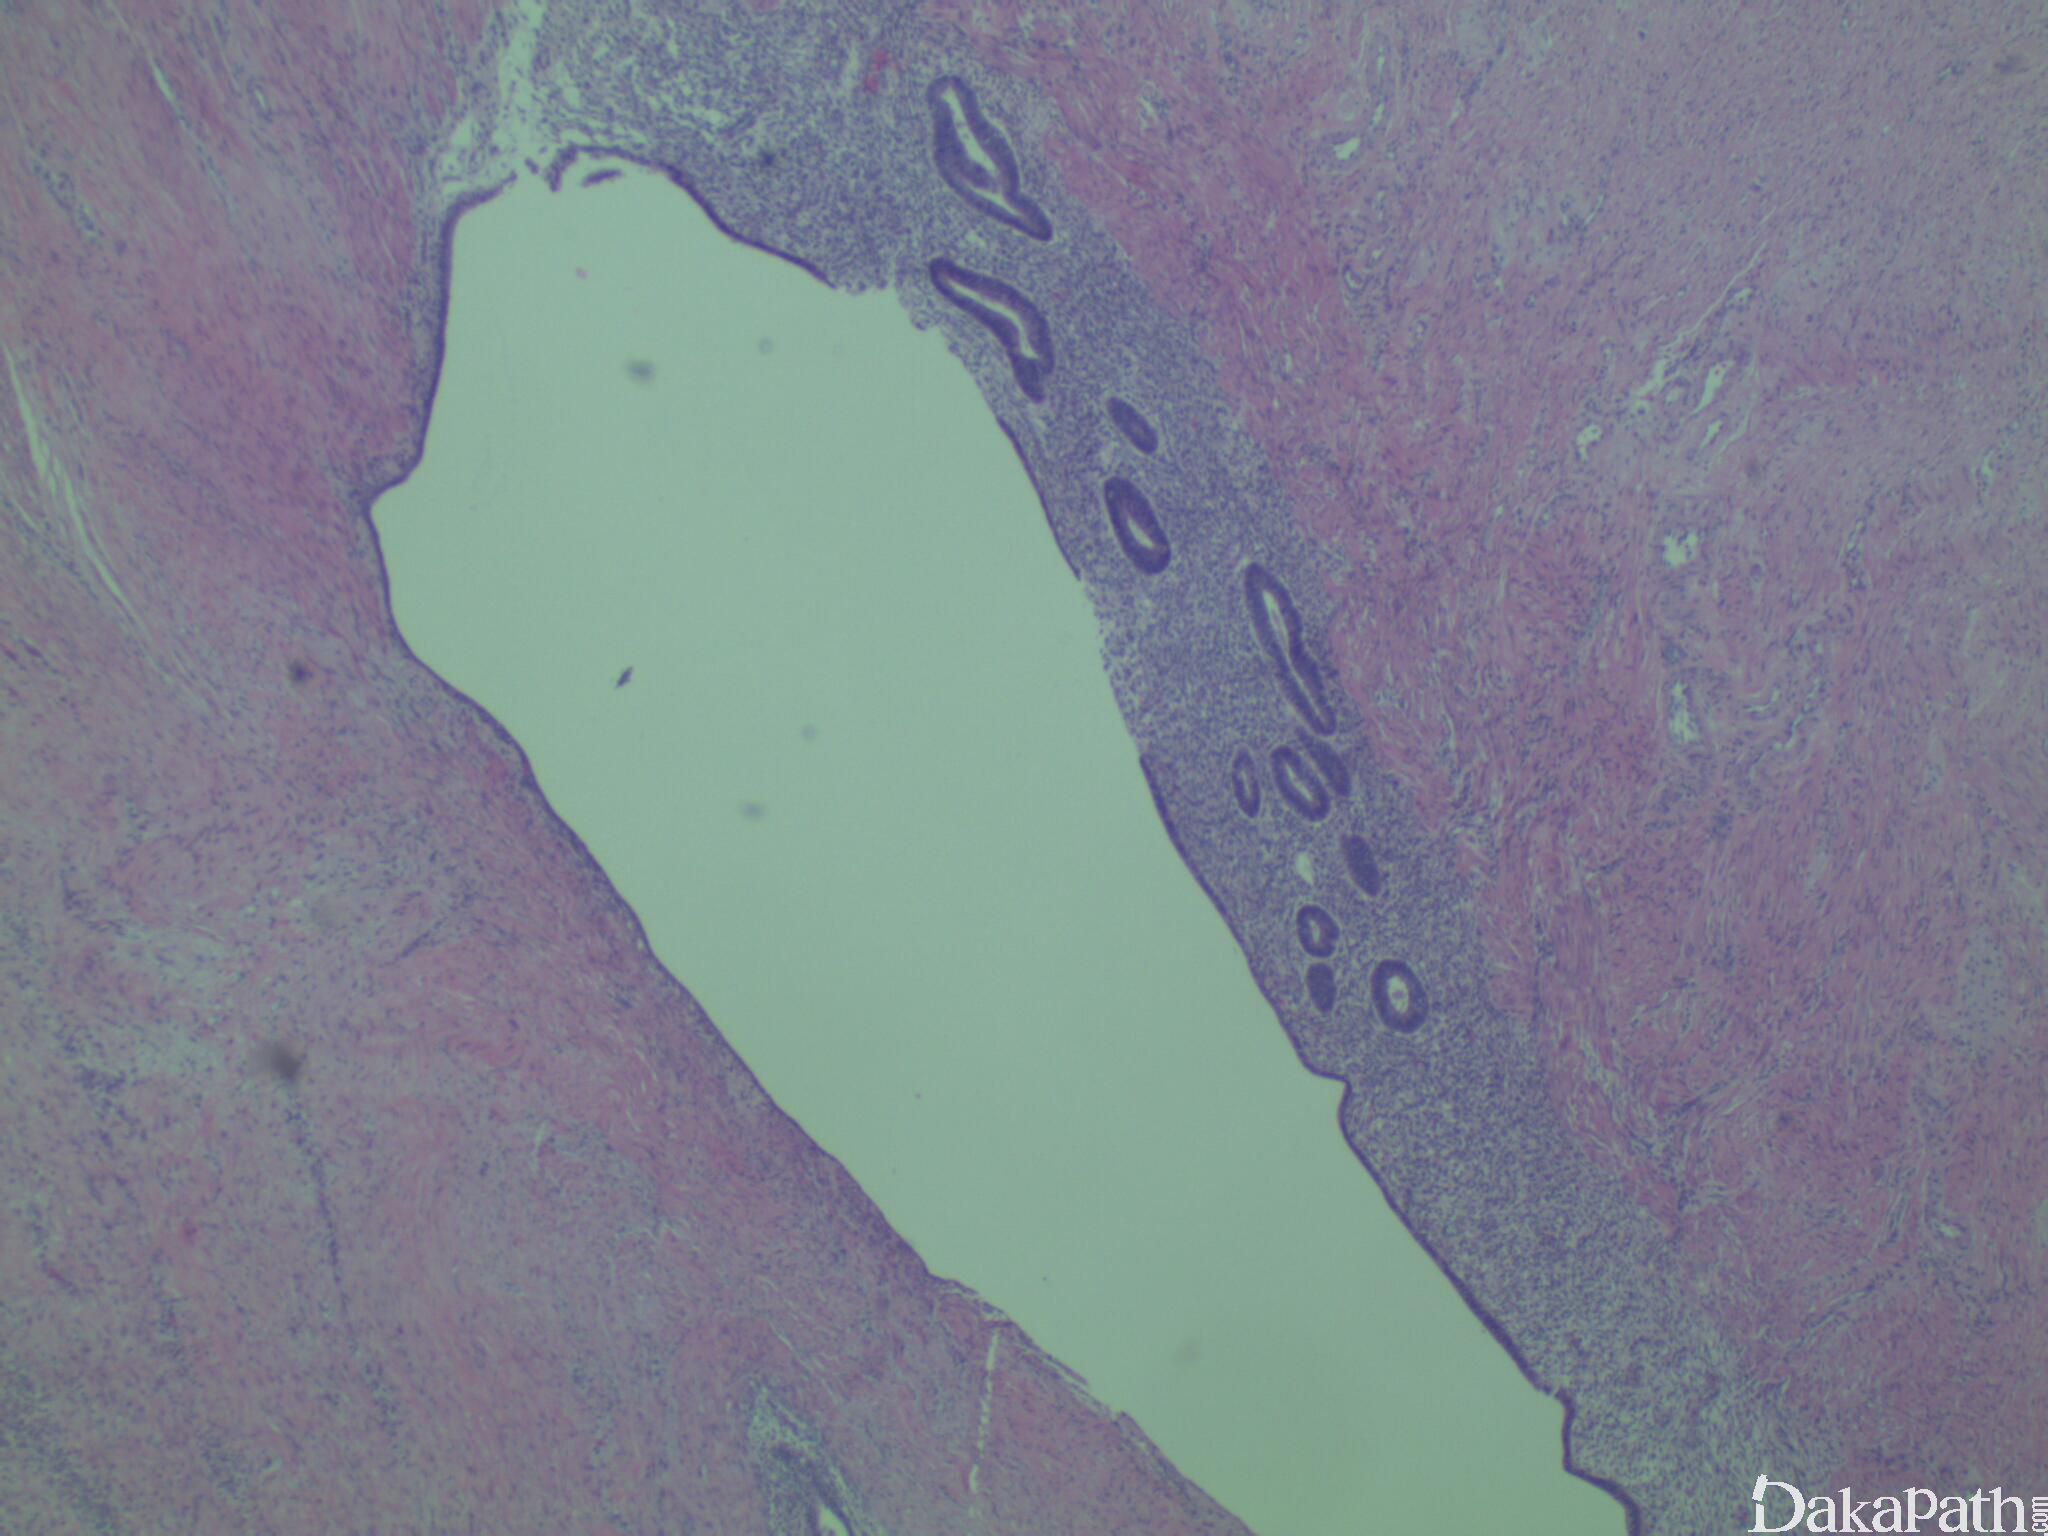

组织学可见界限清楚的子宫内膜腺体及多少不等的子宫内膜间质,腺体衬覆假复层柱状上皮,间质位于腺体周围由致密小的梭形细胞组成,温和间质细胞胞浆稀少,可显示出血、吞噬含铁血黄素的巨噬细胞或假黄色瘤样改变,孕期女性可见蜕膜样变

被覆黏膜的反复性炎症及溃疡可导致慢性结肠炎的特点,隐窝结构扭曲。由于固有层纤维肌增生,可见腺体下陷样改变。黏膜下或浆膜下静脉或淋巴管内可见子宫内膜异位。可见显著同心性平滑肌增生及肥大,继发性的神经肥大及固有肌层的纤维化,浆膜炎及浆膜黏连。